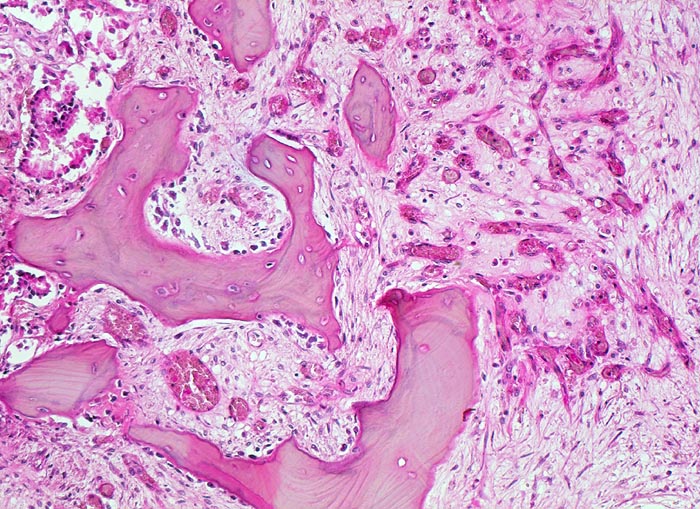

Prostatakarzinom: Knochenmetastase

Knochen, Wirbelsäule

Links im Bild einzelne Karzinomdrüsen. Die erhaltenen Knochenbälkchen zeigen einen gesteigerten Umbau: sie sind herdförmig von einer Osteoblastentapete bedeckt im Sinne eines gesteigerten Anbaus. An einer Stelle ist ein Osteoklast in einer Resorptionslakune sichtbar. Die Markräume rechts im Bild sind mit gefässreichem Granulationsgewebe ausgefüllt.

Bei Autopsie finden sich zahlreiche, teils osteoplastische, teils osteolytische Metastasen im Bereich der Wirbelsäule. Die Karzinomdrüsen sind immunhistochemisch positiv für Prostata spezifisches Antigen.

Bekanntes metastasierendes Prostatakarzinom. St.n. bilateraler Orchiektomie. Diffuse Schmerzen im Bereich der Wirbelsäule. Der Patient verstirbt an einem Myokardinfarkt.